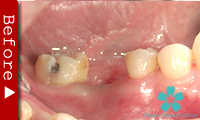

歯を一本だけ失った場合

“失われた1本の歯根の代理品”としてインプラントを1本だけ使って失った歯の部分を修復する方法は、最も洗練された治療方法であり、審美的にも満足のいく結果が得られます。

1本のインプラントによってあたかも自分の天然歯のように自然に感じられます。顎骨の”萎縮”の心配もなく、本来の骨量を維持できます。

ブリッジを入れる時のように、健康な隣の歯を削る必要がありません。